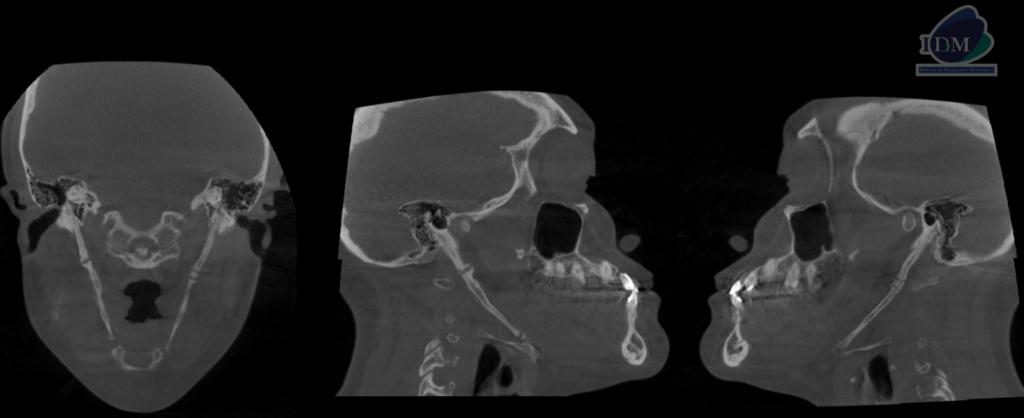

CORTES CORONALES Y SAGITALES

Así mismo en la tomografía volumétrica de haz se confirma dicha mineralización, la cual se extiende desde base de cráneo hacia las astas menores del hueso hioides y presentado un patrón de mineralización pseudoarticulada.

- Mineralización bilateral de la cadena estilohioidea del tipo pseudoarticulada.